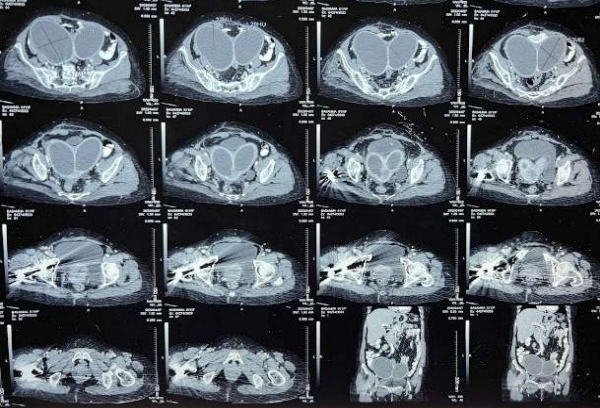

A 63-year-old, fit (ECOG 1) postmenopausal lady, G4P4A0, presented with postmenopausal bleeding with concurrent white discharge per vagina for four months and a history of lower abdominal pain for three months. She underwent surgery with internal fixation for a fracture of the right neck of her femur four years ago. She had no history suggestive of any co-morbidities. Clinically, there was an infiltrative lesion of size 3 x 3.5cm, destroying most of the cervix involving all the fornices and upper 1-1.5cm of the left lateral and posterior vaginal wall. The left parametrium was medially involved with the disease. A biopsy confirmed malignancy, and the histology was squamous cell carcinoma. Local imaging revealed left HUN, making the final diagnosis of IIIB, apart from the bicornuate uterus (Figure 1), with hydrometra in both cornua. The intramedullary nail (Figure 2) was a contraindication for MRI. Her family history was negative for miscarriages.

Figure 1: CT sections show a bicornuate uterus with hydro/pyo metra. The artefacts in the right proximal femur are due to the intramedullary implant.

Figure 2: The implant (in the head, neck & proximal femur) is highlighted with cyan arrows.